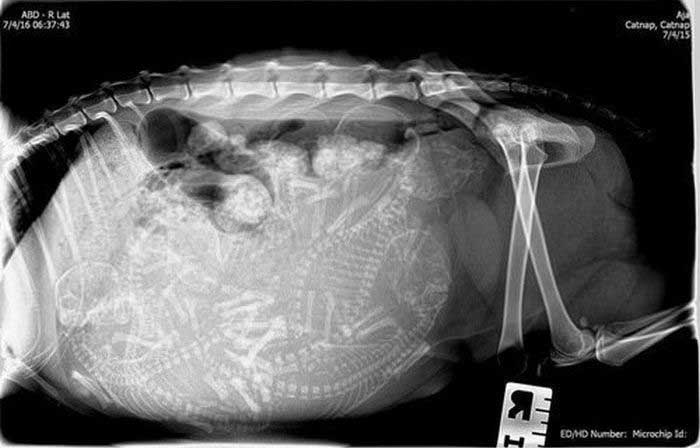

4. イヌ

6. ネコ